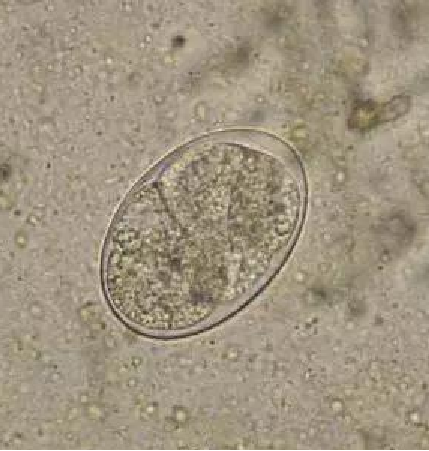

十二指肠钩虫线虫和美洲板口线虫